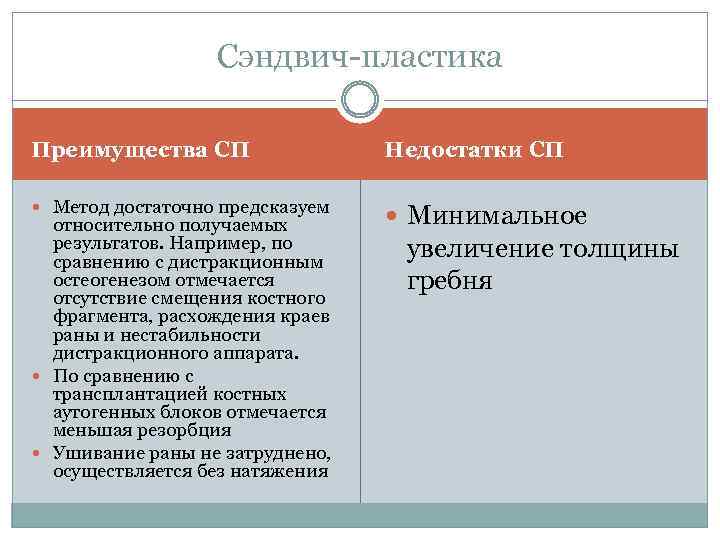

Сэндвич пластика Этот метод применяется в целях реконструкции альвеолярной части нижней челюсти при вертикальной атрофии. Недостаточная высота кости затрудняет установку имплантатов или делает ее невозможной. На нижней челюсти для преодоления анатомических ограничений, в частности со стороны нижнечелюстного канала, могут быть использованы мембрана с титановым усилением, аутогенная кость или заменители кости, дистракционный остеогенез, вертикальная направленная костная регенерация, трансплантация аутогенных костных блоков, мобилизация нижнего альвеолярного нерва и установка коротких имплантатов. Изначально метод применялся для устранения резорбции костной ткани в переднем отделе НЧ. Ряд авторов отмечают положительные результаты применения сэндвич пластики в боковых участках НЧ.

Впервые методику сэндвич остеотомии в сочетании с аутогенными костными блоками описал D. Schettler в 1976 году. Данная методика предполагала проведение одного горизонтального и двух вертикальных распилов в области между подбородочными отверстиями, коронарное смещение костного блока и введение в полученное отверстие аутогенного костного трансплантата. Панин разработал методику математического планирования операции сэндвич пластики. Уровень смещения костного лоскута рассчитывается заранее с учетом размеров, формы и положения будущих ортопедических конструкций, межокклзионных взаимоотношений. Это позволяет максимально точно смоделировать костную «основу» , улучшив прогноз лечения паиентов с применением дентальных имплантатов. Большую роль в успехе реконструкции и последующей имплантации играет количество костной ткани над нижнечелюстным каналом. Небольшая высота кости над нижнечелюстным каналом может быть причиной парестезии в послеоперационном периоде.

Сэндвич пластика Преимущества СП Недостатки СП Метод достаточно предсказуем Минимальное относительно получаемых результатов. Например, по сравнению с дистракционным остеогенезом отмечается отсутствие смещения костного фрагмента, расхождения краев раны и нестабильности дистракционного аппарата. По сравнению с трансплантацией костных аутогенных блоков отмечается меньшая резорбция Ушивание раны не затруднено, осуществляется без натяжения увеличение толщины гребня